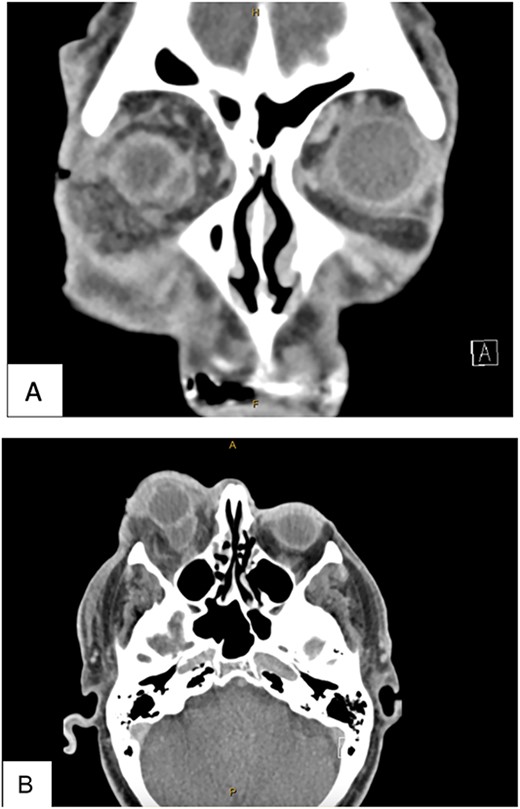

Computed tomography imaging (Fig. 3) showed a 11 × 15 × 14 mm peripherally enhancing collection at the posteroinferior aspect of the right globe concerning for an orbital abscess or infected orbital cyst, with associated retroorbital fat stranding and thickening of the lateral rectus.

This CT was taken post lateral canthotomy. (A) CT Head with Contrast Coronal View. (B) CT Head with contract axial view. Both views show an 11 × 15 × 14 mm peripherally enhancing collection abutting the posteroinferior aspect of the right globe. There is associated retrobulbar fat stranding. There is thickening and enhancement of the lateral rectus muscle. The right optic nerve sheath shows enhancement but no signs of effusion.